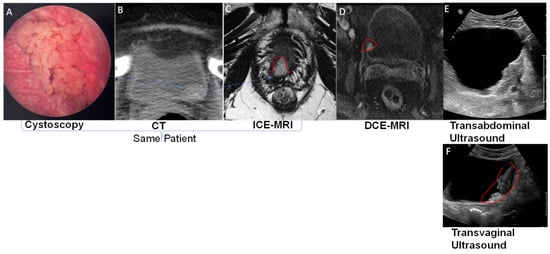

- Connell, M.; Dhir, R.; Moon, C.H.; Biatta, S.; Tarin, T.; Maranchie, J.; Tyagi, P. Discrimination of cystitis cystica from bladder cancer by intravesical contrast-enhanced magnetic resonance imaging (ICE-MRI). Can. Urol. Assoc. J. 2022, 16, S158. [Google Scholar] [CrossRef]